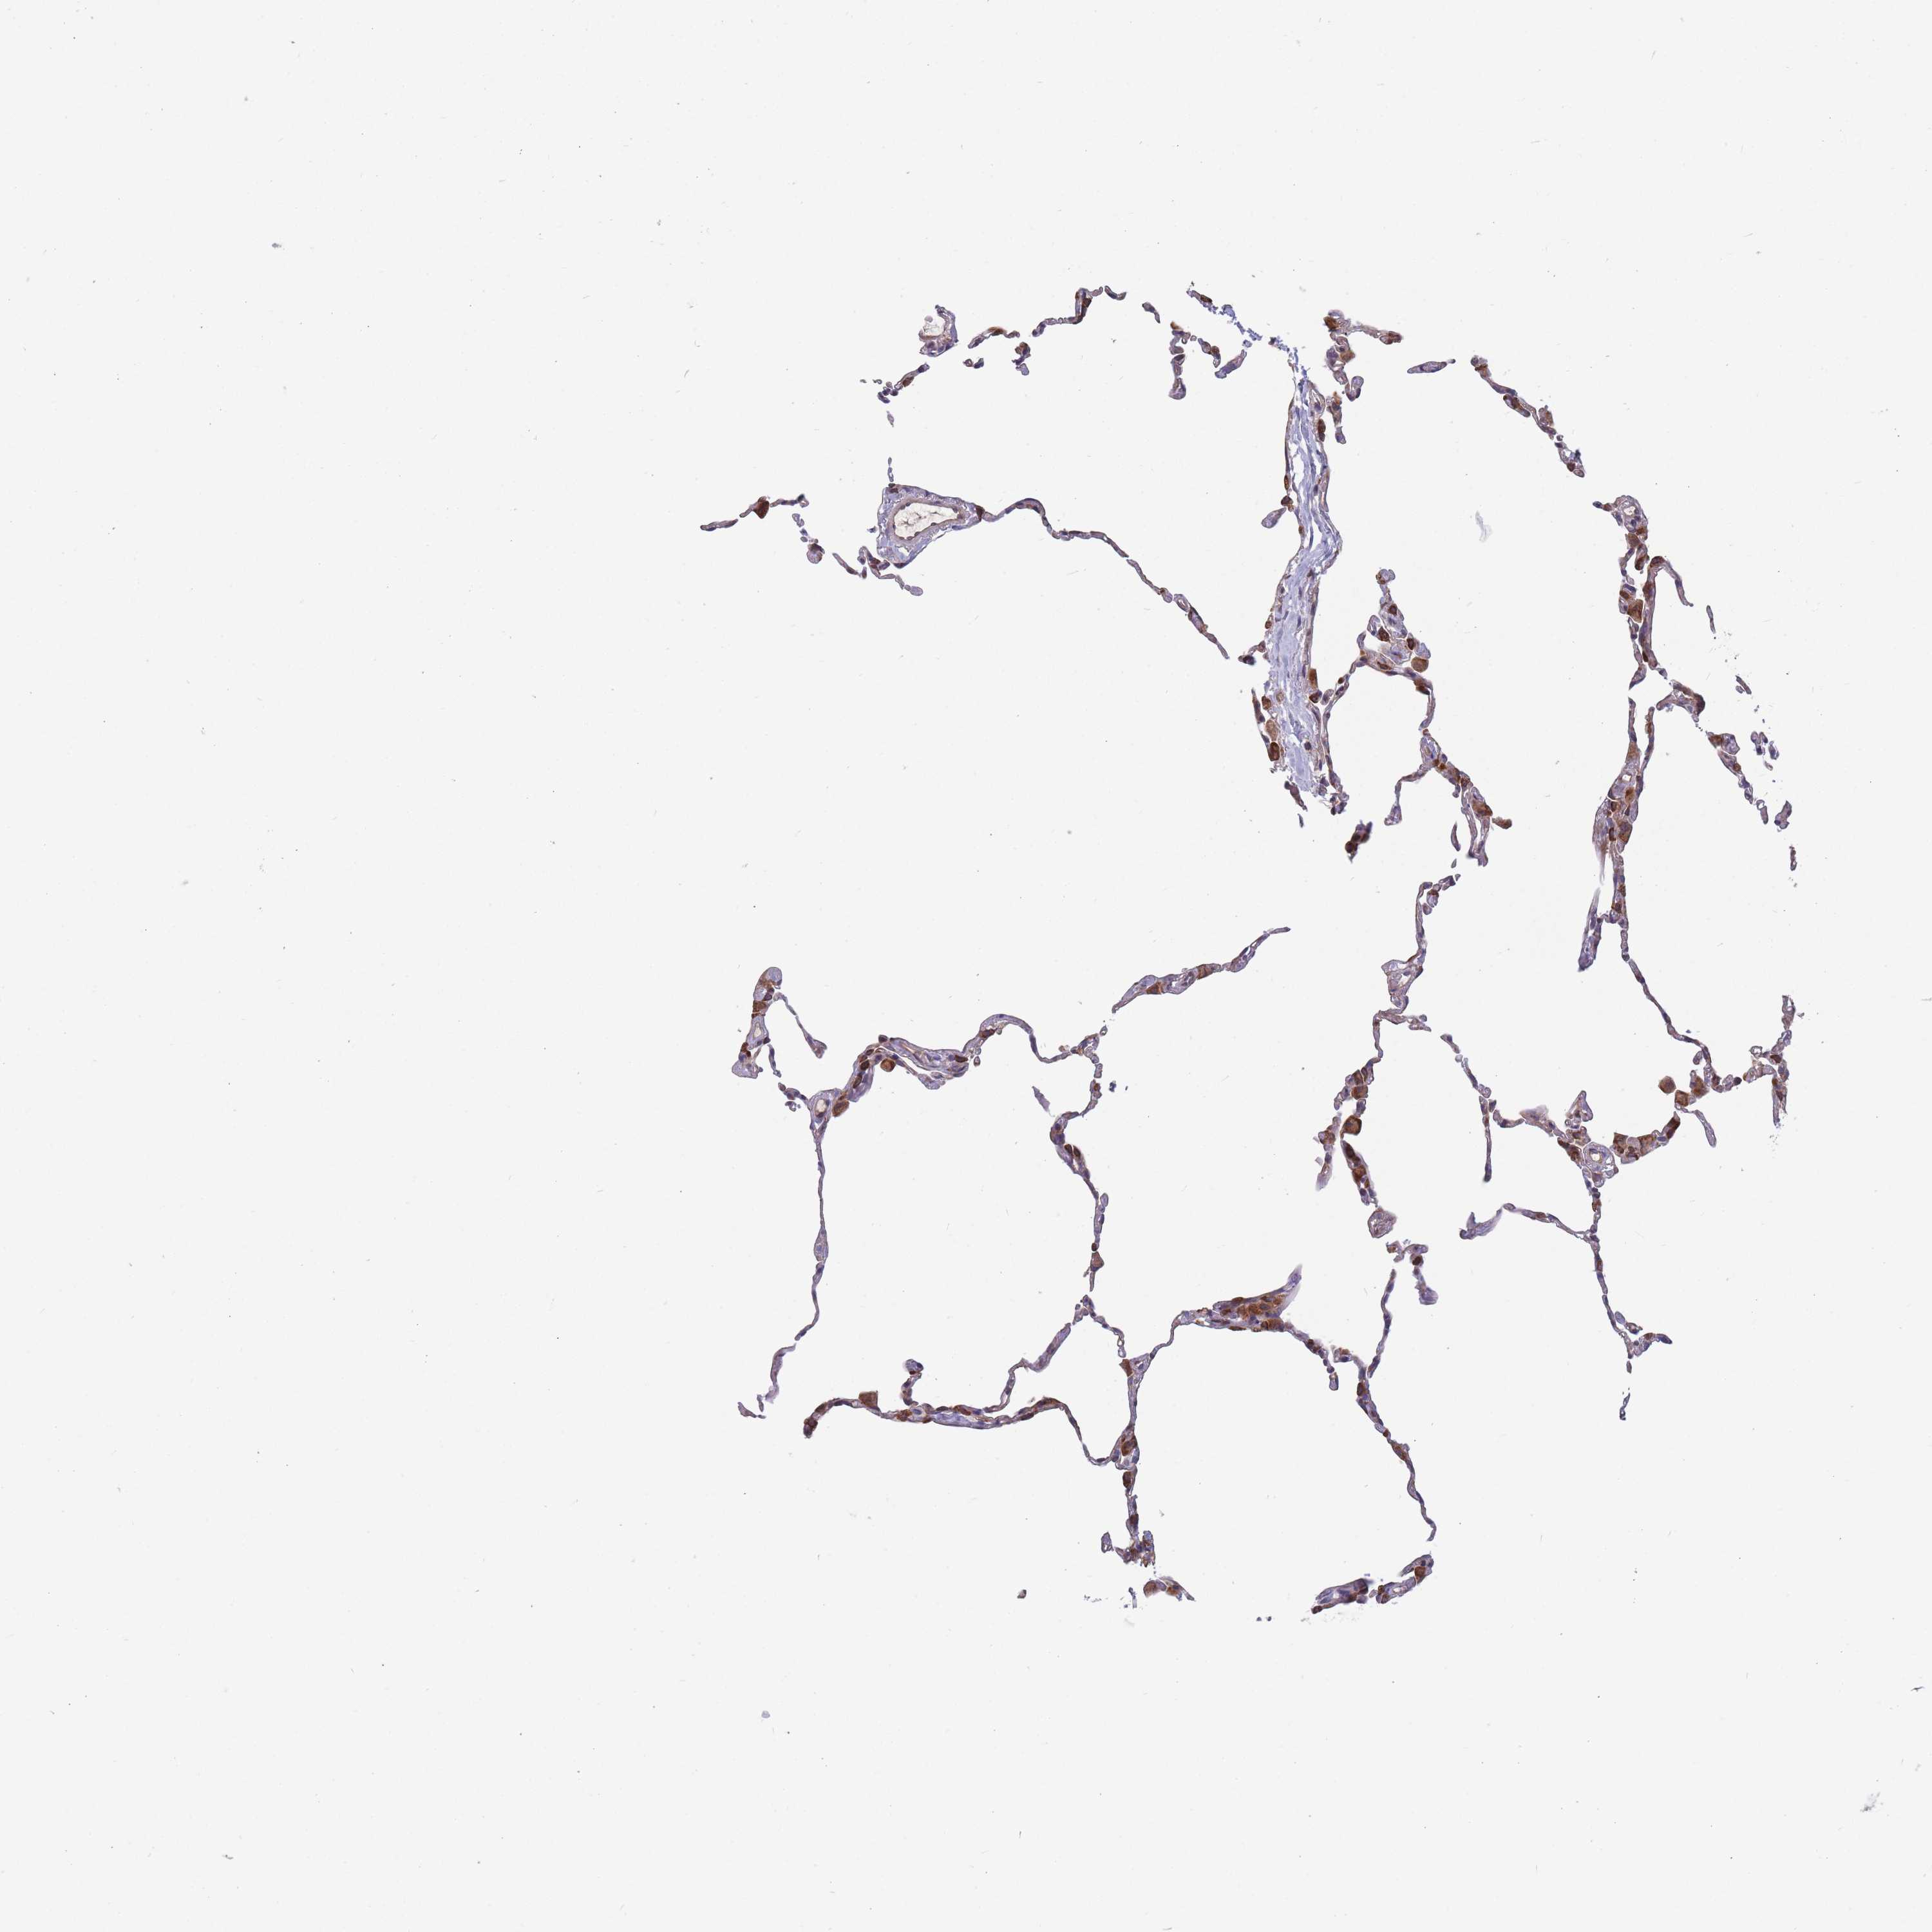

Antibody staining in the annotated cell types in the current human tissue is reported as not detected, low, medium, or high. This score is based on the staining intensity and fraction of stained cells.